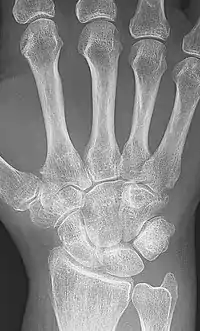

X-rays of the hands and feet are generally performed when many joints affected. In RA, there may be no changes in the early stages of the disease or the x-ray may show osteopenia near the joint, soft tissue swelling, and a smaller than normal joint space. As the disease advances, there may be bony erosions and subluxation. Other medical imaging techniques such as magnetic resonance imaging (MRI) and ultrasound are also used in RA.[20][67]